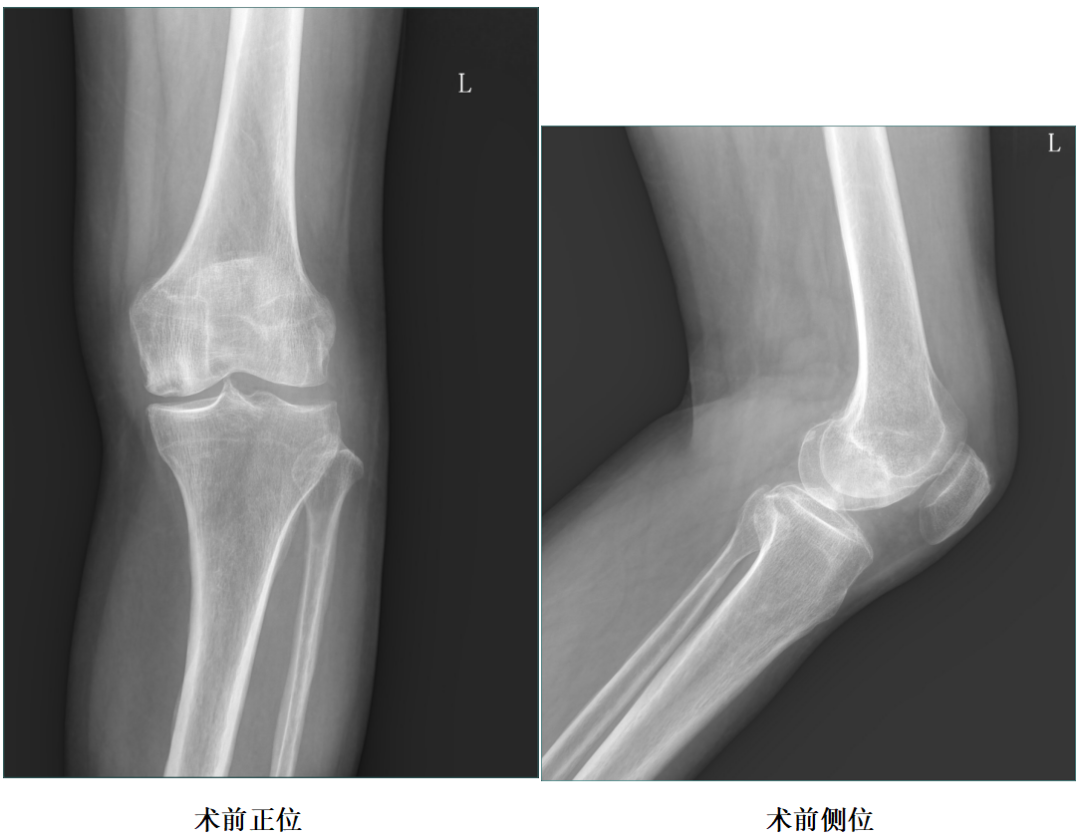

女性患者,70岁,左膝关节疼痛伴活动受限1年余。

体格检查:左膝轻度内翻畸形,约5°,无屈曲畸形。屈曲20°外翻应力下内翻畸形可纠正,屈曲90°可自行纠正。内侧关节间隙处压痛阳性。活动度:0°~120°。

X-Ray:左膝内侧间隙狭窄,站立位内侧间隙消失,外侧间隙正常,膝关节稳定。

CT:左膝内侧髁见囊状透亮影,内侧关节间隙狭窄。

诊断:左膝关节内侧间室OA,左膝关节自发性骨坏死。

二、术前X片